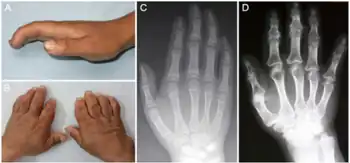

| a-d) Characteristics of child and adult Kashin-Beck disease individuals | |

Kashin–Beck disease (KBD) is a chronic, endemic type of osteochondropathy (disease of the bone) that is mainly distributed from northeastern to southwestern China, including 15 provinces.[1] Tibet currently has the highest incidence rate of KBD in China.[1] Southeast Siberia and North Korea are other affected areas.[1] KBD usually involves children ages 5–15. To date, more than a million individuals have suffered from KBD.[2] The symptoms of KBD include joint pain, morning stiffness in the joints, disturbances of flexion and extension in the elbows, enlarged inter-phalangeal joints, and limited motion in many joints of the body.[3] Death of cartilage cells in the growth plate and articular surface is the basic pathologic feature; this can result in growth retardation and secondary osteoarthrosis.[1] Histological diagnosis of KBD is particularly difficult; clinical and radiological examinations have proved to be the best means for identifying KBD.[4] Little is known about the early stages of KBD before the visible appearance of the disease becomes evident in the destruction of the joints.[4]

The clinical presentation of this condition is as follows:[7]

- Restricted movement

- Pain in joints

- Large joints

- Varus deformity of hip

- Thick fingers

In terms of the diagnosis of the condition, it is done via radiographical studies (x-ray)[7]